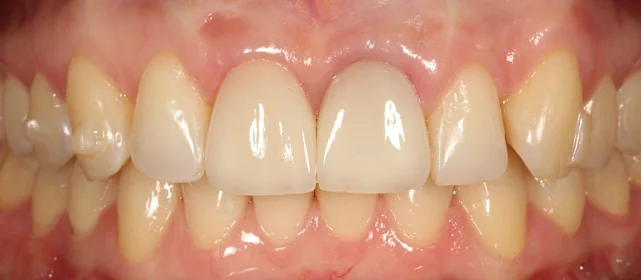

Результат

Зубы выровнены, скученность устранена, прикус исправлен, линия смыкания нормализована. Ретейнер установлен на нижнюю челюсть. На верхней ретейнер не ставили — на передних зубах коронки, вместо этого изготовлены ретенционные капы на обе челюсти. Пациентка направлена к ортопеду для замены коронок.

Решение: Поставили элайнеры Click на обе челюсти. Основной набор — 31 капа, плюс два дозаказа: 26 и 7 кап, итого 64. При этом лечение уложилось в 20 месяцев — быстро для такого объёма работы. Расширили дуги, убрали скученность, исправили прикус, выровняли линию смыкания. Ретейнер поставили только на нижнюю челюсть. На верхней от ретейнера отказались сознательно — на передних зубах коронки, и проволока там не ляжет корректно. Вместо этого изготовили ретенционные капы на обе челюсти. Ортопедию — замену старых коронок — пациентка будет проходить у себя в городе.